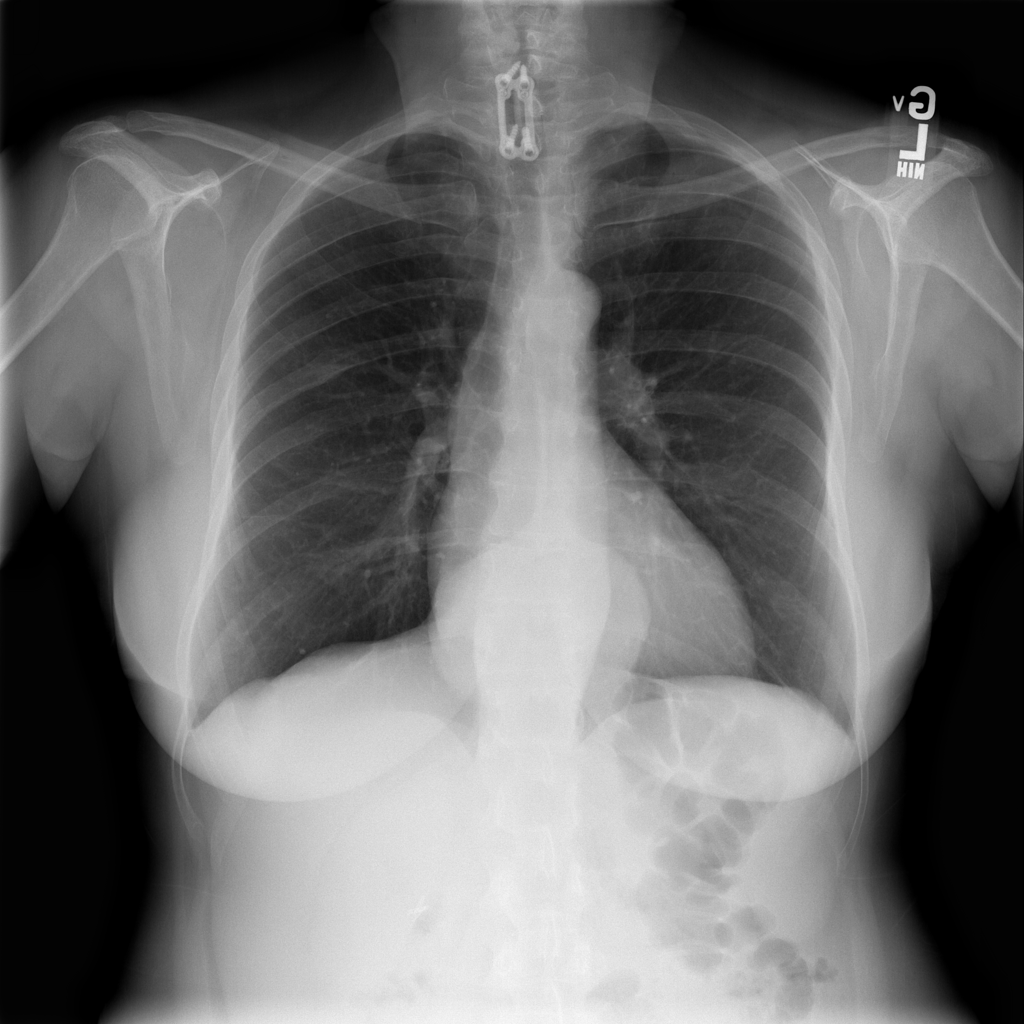

Showing up to 90 reference images for Hernia.

PAT-4F7E · IMG-000Hernia

PAT-4F7E · IMG-000

PA